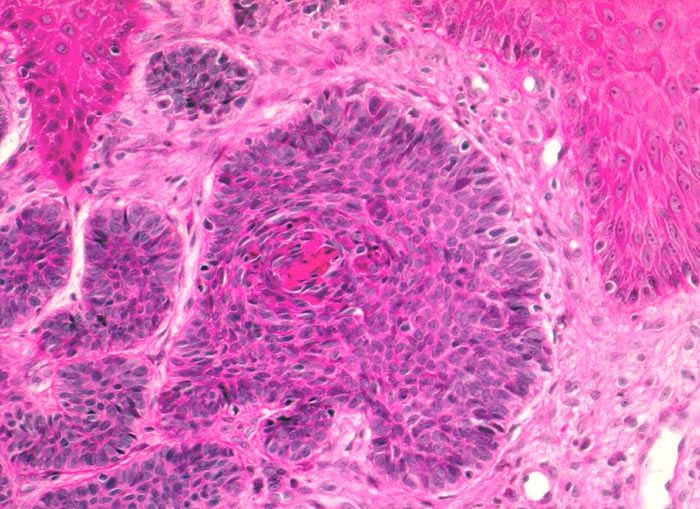

PathoPic ID 5102 - Basaliom

Basaliom

maligner Tumor

Haut, Kopf

Haut

Ein Teil der Tumorzellplatten zeigt im Zentrum eine angedeutete

Verhornung. Die zytoplasmaarmen Tumorzellen sehen sehr ähnlich aus wie die

Basalzellen der Epidermis.

Derber weisser, leicht erhabener Knoten an der Nase.

Histologie

200